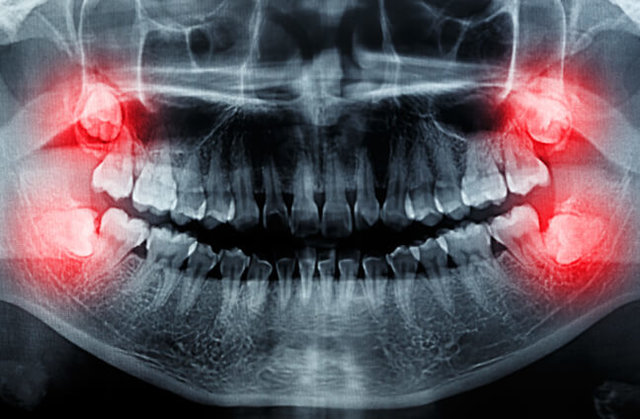

دندانهای عقل در انسان برای بهتر خرد کردن غذاهای سفت مانند گیاهان خام، گوشت و مغزها تکامل پیدا کردند اما با نرمتر شدن رژیم غذایی و بزرگتر شدن مغز در گونه انسانی ما، جمجمهها بزرگتر و آروارهها کوچکتر شدند؛ آنچه باعث شد دندانهای عقل چون مهمانی ناخوانده در دهان باقی بمانند که هم فضایی گرانبها را اشغال کردهاند و هم درد و ناراحتی ایجاد کنند و هنوز نفهمیدهاند که دیگر قدمشان روی چشم نیست! آنها با ایجاد تراکم بیش از حد دندانها در فک دردی مزمن به وجود میآورند و اگر هم نهفته و پنهان در لثه بمانند (بر اثر فشار به لثه یا دندانهای دیگر) ممکن است مشکلات سلامتی مانند پوسیدگی و عفونت ایجاد کنند. از طرفی افراد گرفتار با عوارض دندان عقل اغلب برای جویدن مشکلاتی دارند و دهانشان بوی بدی میدهد.

نتیجه اینکه کشیدن دندان عقل (ادنتکتومی) بسیار رایج است و مردم در سراسر جهان چندین دهه است که انتخابشان این است که از طریق جراحی دندان عقل را از دهانشان خارج کنند، زیرا این دندانها قابلیت خاصی ندارند و میتوانند مشکلاتی برای سلامتی ایجاد کنند.

بیلی میگوید: درباره خارج کردن دندانهای عقل نهفته و پنهان در حالی که هیچ بیماری یا عارضهای ایجاد نکردهاند، اختلاف نظر وجود دارد. برخی از جراحان به منظور پیشگیری از بروز مشکل در آینده دندان عقل را میکشند، در حالی که عوارض جانبی این عمل قابلتوجه است و تنها به درد محدود نمیشود؛ بلکه مشکلاتی بلندمدت مانند بیحسی لبها، چانه و زبان را هم به دنبال دارد.